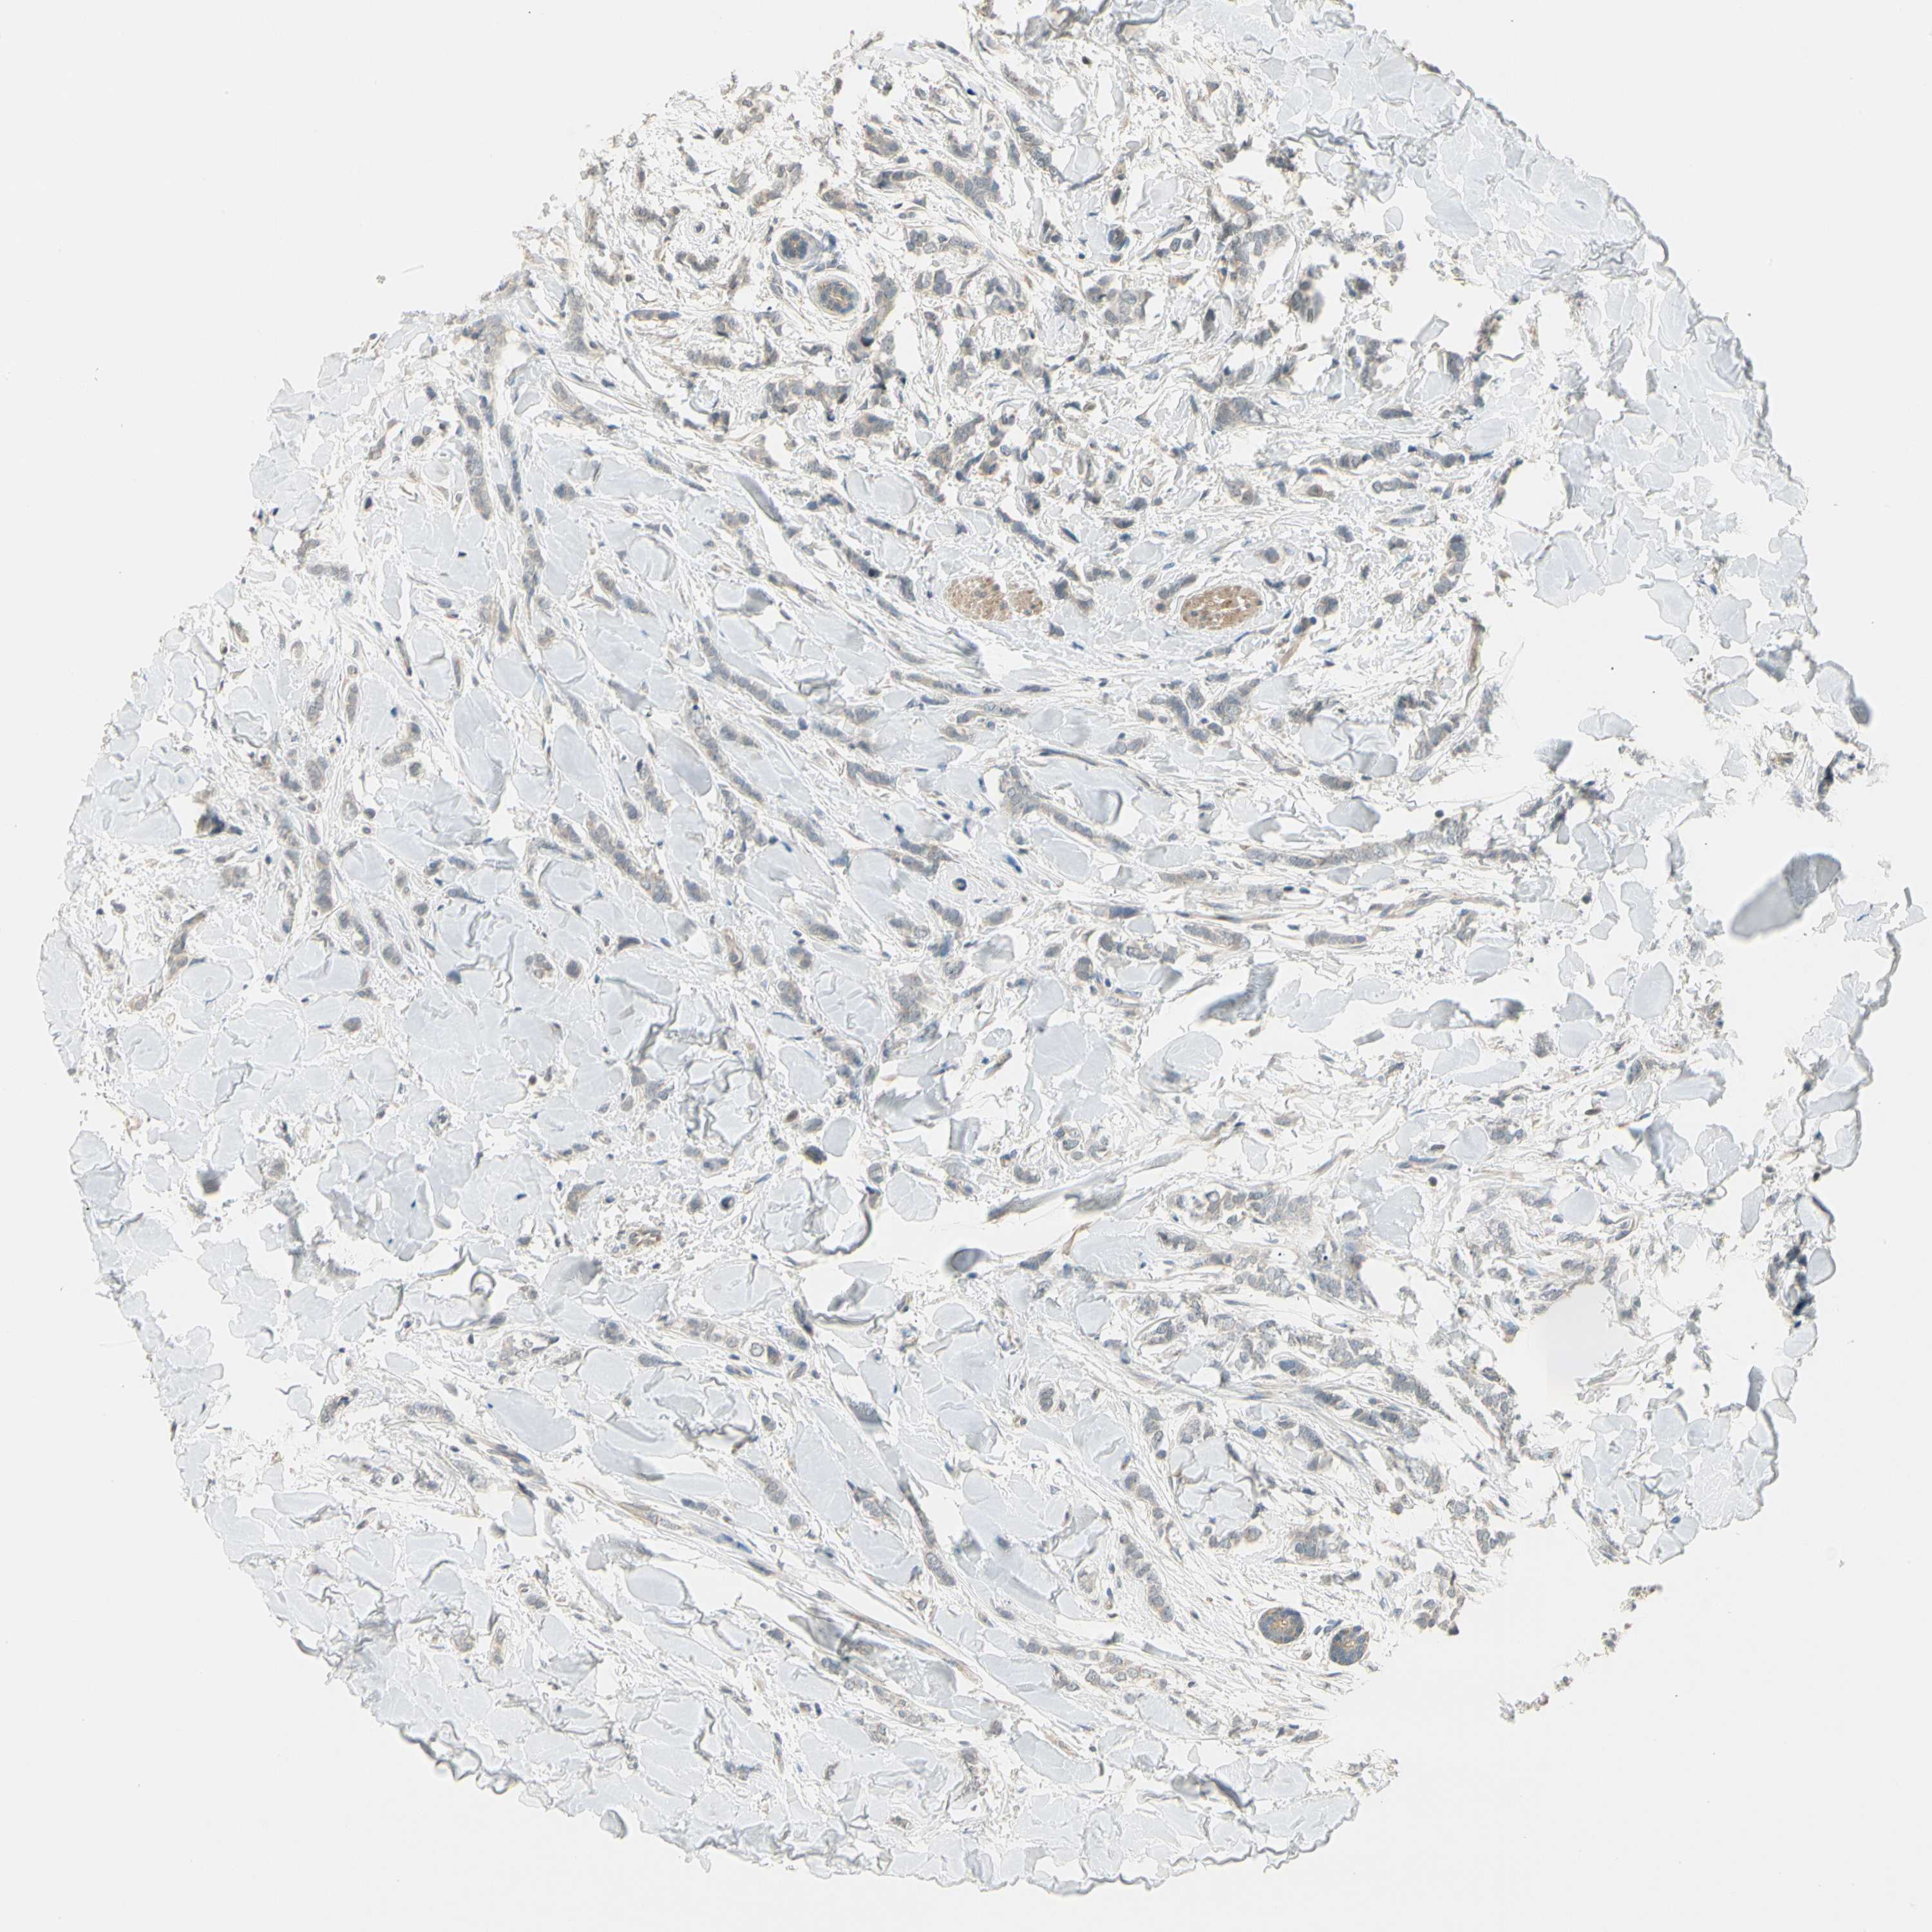

BRCA TCGA BRCA VALIDATION PROTEIN EXPRESSION